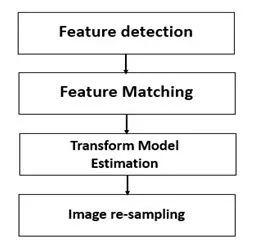

图像配准通用流程

通常,图像配准技术包括四个方面:变换模型、特征空间、相似性测度、搜索空间和搜索策略。依据这四个特性,图像配准的步骤一般可分为以下五个步骤:

以基于特征的图像配准通用流程为例:

基于特征的图像配准通用流程

1.Feature detection: 特征检测

特征检测是图像配准过程的一项重要任务。根据问题的复杂性,通常分为手动或自动检测,但通常优先选择自动特征检测。

2.Feature matching: 特征匹配

该步骤基本建立在对待配准图像与在参考图像中检测到的特征之间的对应关系上。

除了特征之间的空间关系之外,还采用不同的特征描述符( feature descriptor)和相似性度量来确定配准的准确性。

必须合理地配置特征描述符,使得它们在任何退化时仍保持不变,与此同时,它们需要不受噪声影响且能适当区分不同的特征。

3.Transform model estimation: 图像变换模型的评估

为配准浮动图像与参考图像,需要估计映射函数的参数。使用从前一步骤获得的对应特征来计算这些参数。

映射函数的选择,取决于图像采集过程和预期图像变形的先验知识。在没有任何先验信息的情况下,必须确保模型的灵活性。

4.Image transformation/re-sampling: 图像变换

对浮动图像使用映射进行图像变换来配准。